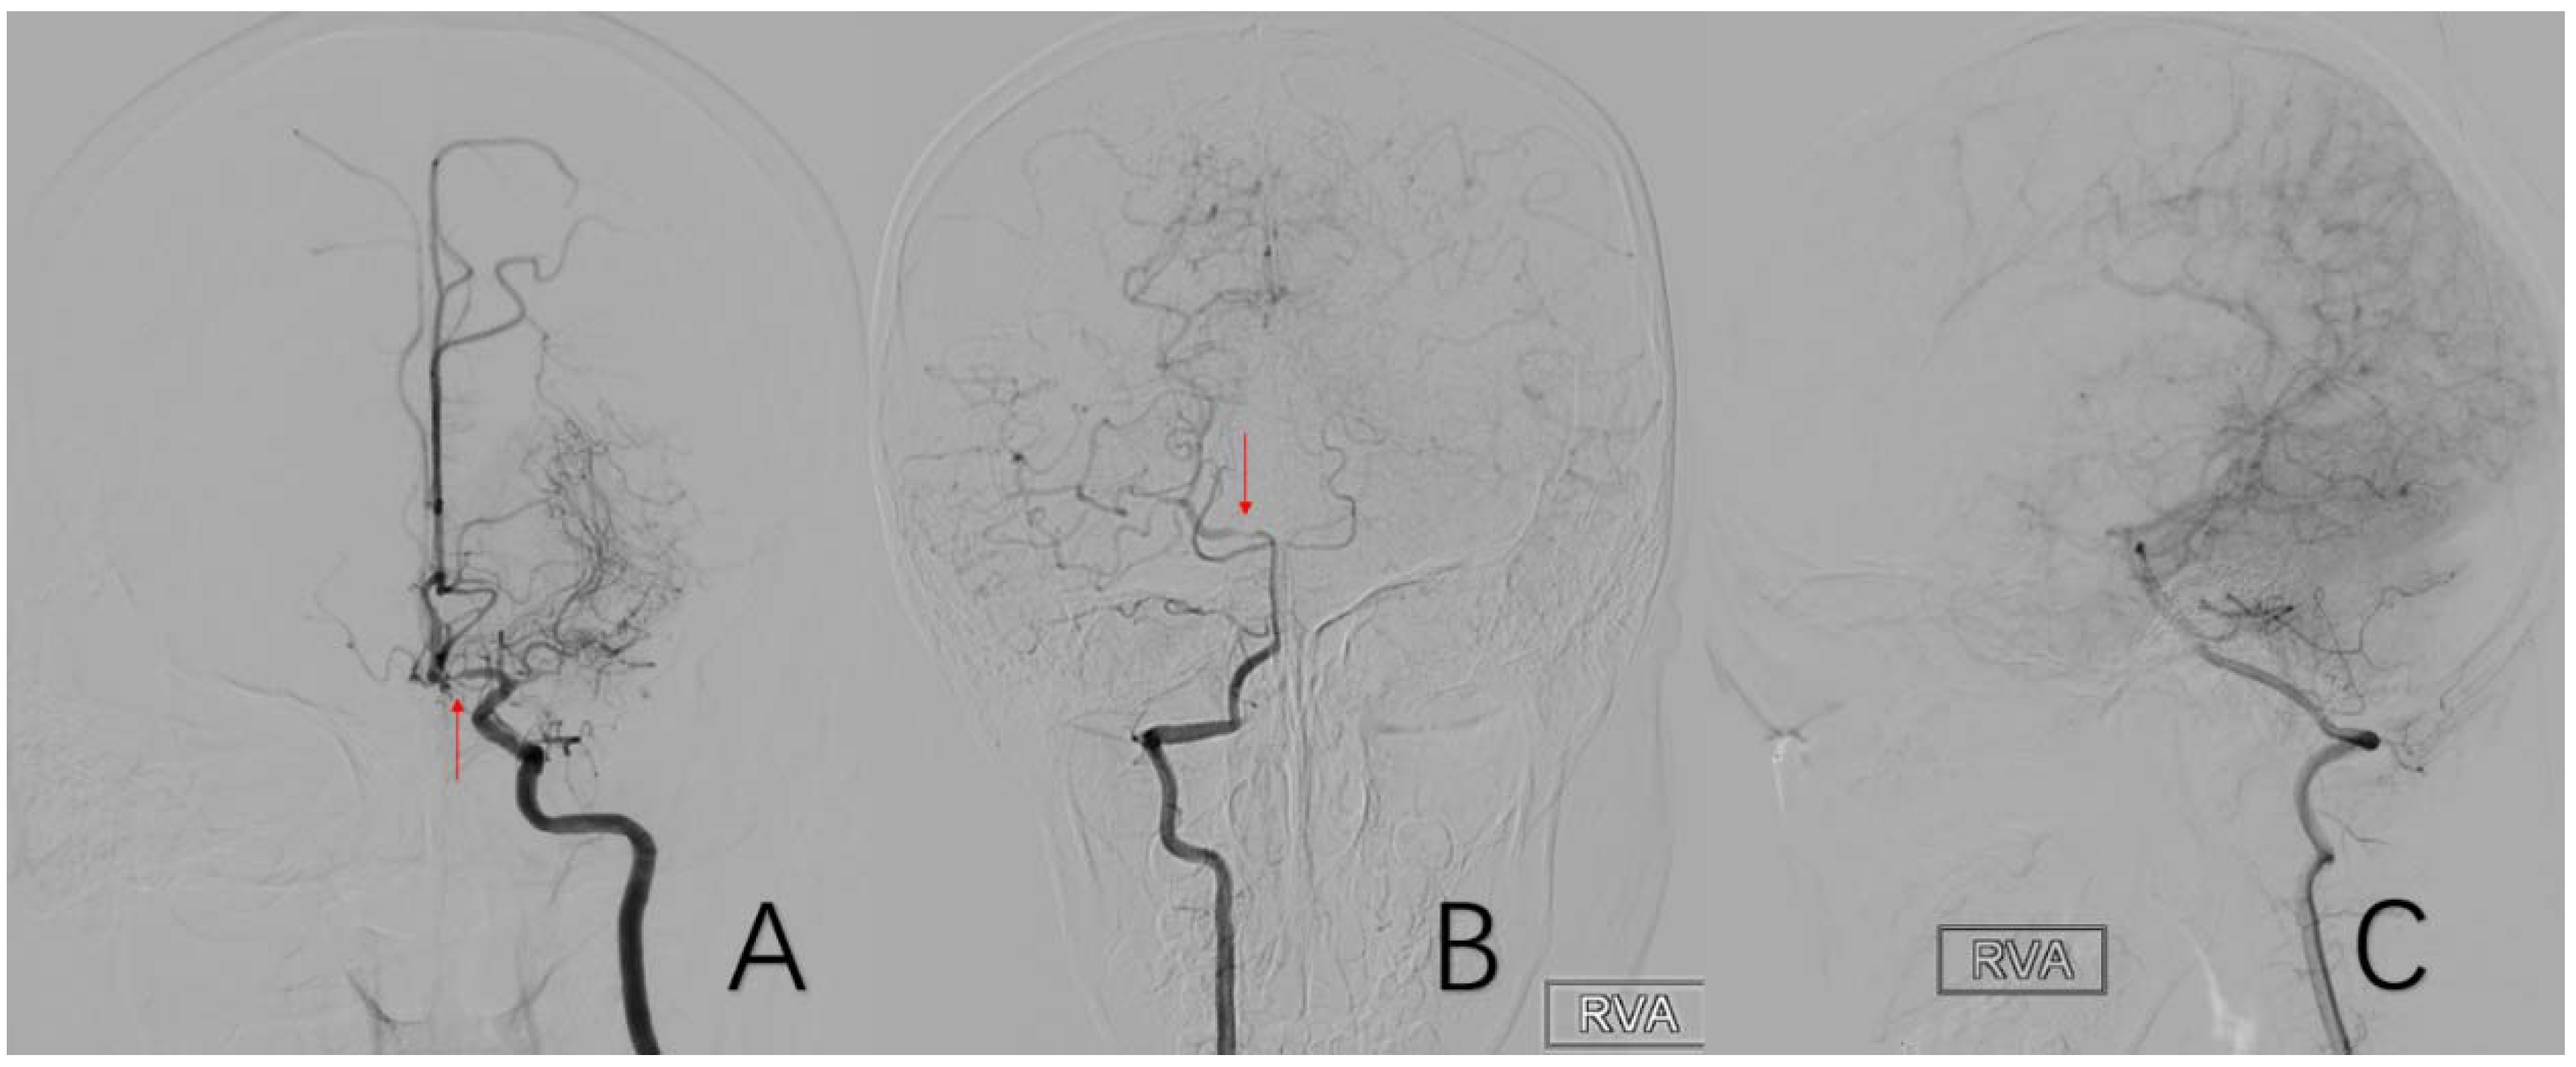

2.3.10. Factor 5 Posterior Circulation Compensation

2.3.11. Factor 6 Unstable Compensation

2.3.12. Factor 7 Extracranial Arterial Compensation